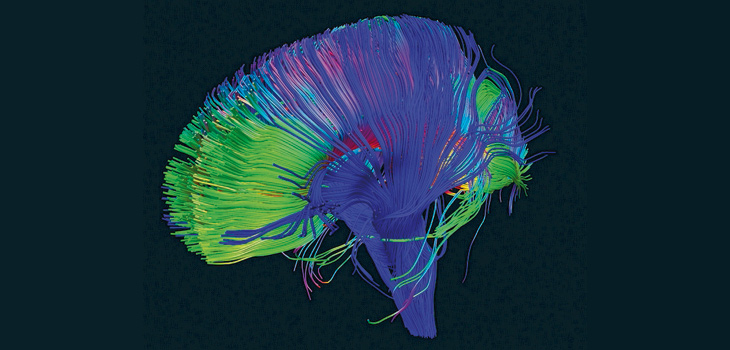

Descubren el posible origen de la consciencia en el cerebro

Investigadores canadienses han descubierto que el cerebro humano es capaz de transmitir información a través de la luz. Puede producir más de 1.000 millones de biofotones por segundo, un volumen suficiente para transmitir un gran número de bits con información, así como de generar procesos cuánticos capaces, hipotéticamente, de generar consciencia.